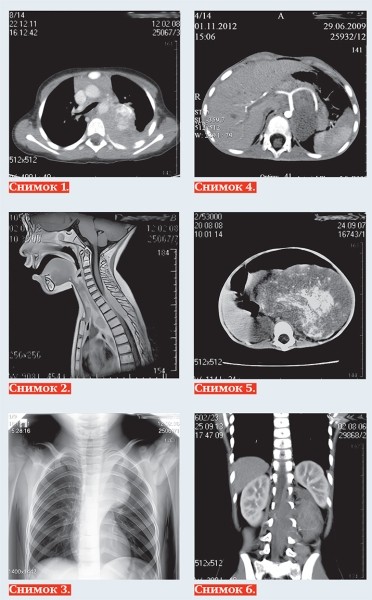

Тканевыми характеристиками нейробластомы являются: мягкотканная масса +25+35 HU на КТ (снимок 1), с гипоинтенсивным МР-сигналом на Т1-ВИ, изо/слабогиперинтенсивным сигналом на Т2, Т2 dark fluid — ВИ (снимок 2), негомогенная за счет кровоизлияний, очаговой кальцинации и некротических изменений, с умеренным контрастированием в паренхиматозную фазу, умеренной рестрикцией диффузии на МРТ.

Современная методика МРТ-диффузионного исследования всего тела нацелена на поиск метастазов опухоли. Радионуклидное исследование с I123-метайодбензилгуанидином (MIBG) выявляет и уточняет жизнеспособность опухоли с наибольшей чувствительностью (90 %) и специфичностью (до 100 %). Позитронно-эмиссионная томография с фтордезоксиглюкозой (ПЭТ-ФДГ) используется для дифференциальной диагностики нейроэндокринных опухолей.

Чаще всего нейробластома локализуется паравертебрально в реберно-позвоночной борозде по ходу симпатических ганглиев: в забрюшинном пространстве, надпочечниках, заднем средостении (снимок 3), полости таза, в области шеи. Генерализация опухоли с метастазированием в кости выявляется в 20 % случаев, в печень — 10 %, реже в легкие, головной мозг, подкожную клетчатку, при этом характерно поражение периорбитальных мягких тканей (1–5 %).

К наиболее важным визуально определяемым признакам опухоли (IDRF) относятся: поражение двух и более частей тела, вовлечение в опухоль более 50 % периметра артериального сосуда

(снимок 4), сдавление вены без визуализации ее просвета, инфильтрация прилежащего органа (снимок 5), компрессия трахеи и главных бронхов, инвазия сосудистых ножек почек, распространение в спинно-мозговой канал более трети просвета (снимок 6).